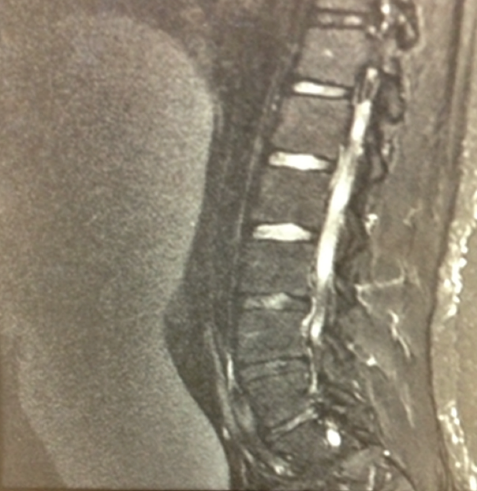

Bisrat Haile, MD; Orlando Carpio, MD; Sameh Abdelaal, MD; Rafael Ilyayev, MD; Rajat Mukherji, MD

A 73-year-old female, nursing home resident, with a past medical history of dementia and breast cancer, was found to have a significant weight loss over a period of 5 months associated with poor appetite. ...